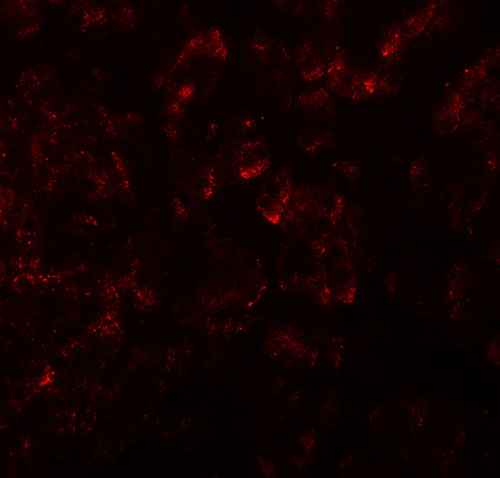

Immunofluorescence of KIRREL2 in human pancreas tissue with KIRREL2 antibody at 20 μg/ml. |